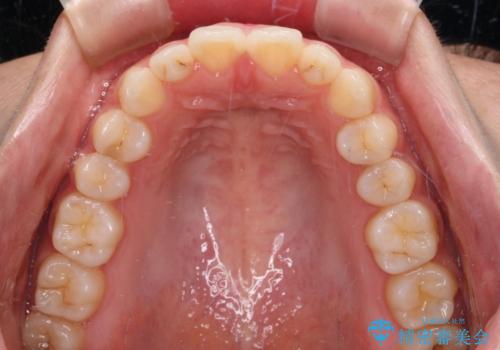

インビザラインを用いた上顎の部分矯正

- 上顎前歯の叢生を気にして来院された患者様です。

下顎前歯や上下奥歯の咬み合わせには殆ど問題がないため、上顎前歯のみを矯正する治療を提案しました。

ワイヤー装置でもインビザラインでも可能でしたが、前歯のみをきれいに排列するのであればインビザラインの方が仕上がりが良いので、インビザライン・ライトにて治療を行うこととしました。

インビザライン・ライトは、製作できるアライナーの枚数に制限があるため、移動可能な量に限りがあります。

一方で、半年から1年程度で治療を終えることができるため、軽度の歯列不正の患者様には大変お勧めです。